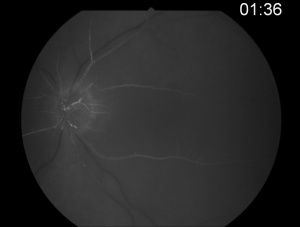

Fluorescein angiography shows a delay in the filling of the retinal arteries and a delayed arteriovenous transit time in the affected areas. The flow of blood in retinal arteries is very sluggish. The front edge of fluorescein (an arterial dye front-the angiographic feature with highest specificity) is seen to travel very slowly to the peripheral retina along the branches of retinal arteries. Complete lack of filling of the retinal vessels is very rare. Delayed choroidal filling should point to an ophthalmic or carotid artery obstruction. Over time, the vessels recanalize and flow reverts to normal, despite the persistence of retinal vessel narrowing. When retinal circulation re-establishes, the retinal fluorescein angiogram may be unremarkable, despite clinically pale retina, and cherry red spot, especially in cases where no emboli or boxcarring is clinically visible.